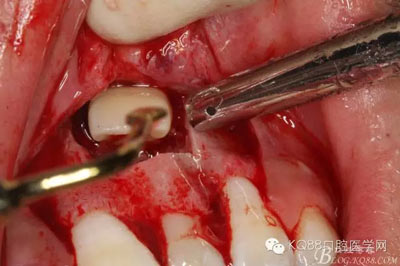

圖5.局部無(wú)痛麻醉下。行唇側(cè)齦溝內(nèi)切口

圖6.雙側(cè)垂直附加切口,形成梯形瓣

圖7.翻瓣、注意是全厚瓣。